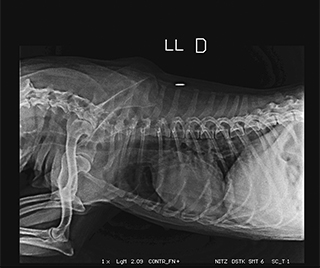

Radiologia Digital Direta / Digital Radiography

As radiografias geradas digitalmente podem ser transmitidas para iPad Apple®, notebooks e smartphones.

iPad com tela Retina Apple® possibilita a visualização das imagens com maior qualidade diagnóstica.

Envio Digital Automático (EDA) permite a distribuição das radiografias sem necessidade de impressão.

O responsável pelo paciente pode receber as radiografias em seu smartphone ou computador.

Radiologistas podem receber as imagens por e-mail para laudo, de forma prática. 100% DIGITAL